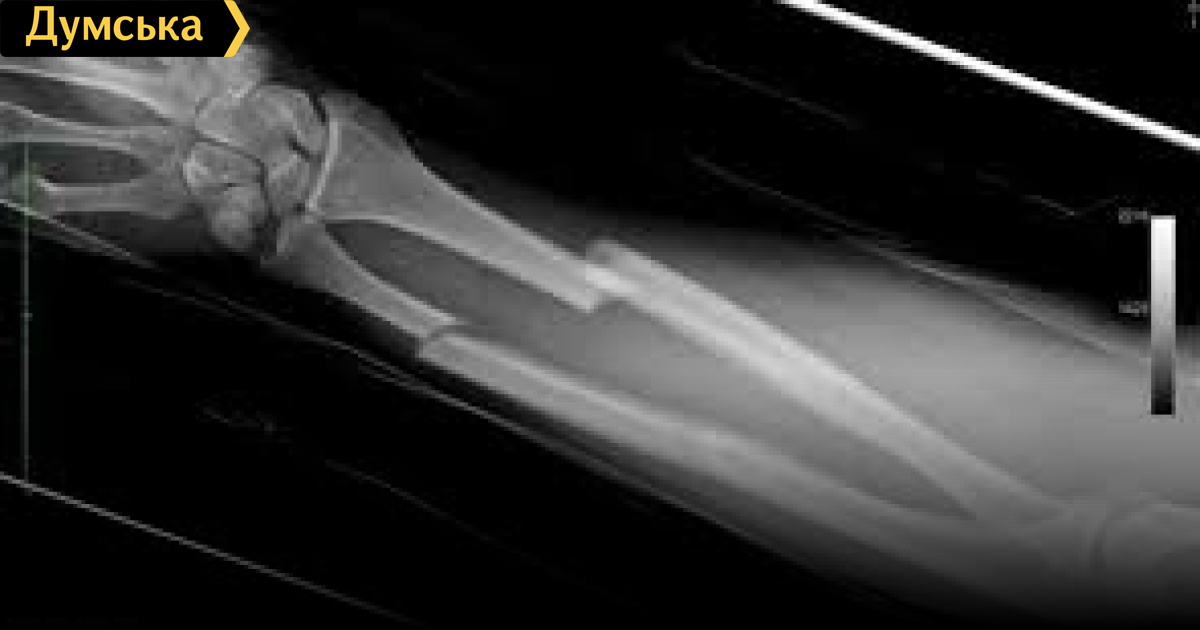

«Сделали рентген. Бесплатно — это входит в заплаченных 50 грн. А дальше отправили на томографию, которая стоит 700 грн, и которую без денег, естественно, делать никто не хотел. А без томограммы врачи делать что-либо отказывались. Мы сделали томограмму -она была готова к 15:00. В итоге в районе 6 вечера, то есть спустя 7 часов ожидания, тещу отвели в операционную и вправили вывих — минут за десять», — сообщил Колисниченко.

МРТ при вывихе? После рентгена? В гонке за баблом совсем совесть потеряли! Пусть Е.А. Григорьев расскажет, каким протоколом при вывихе лучезапястного положена МРТ, нафига заставили купить у врача!! повязку почти за штуку и каким образом анестезиолог применяет типа свои дексалгин и канюлю в/в и заставляет купить в аптеке на возмещение затрат. Где перечень наличия в учреждении лекарств  изделий медназначения, предусмотренный приказом Минздрава? Очень сомневаюсь, что там нет дексалгина и в/в катетеров, зайдите на Прозорро и посмотрите, сколько ГКБ 11 да и все остальные всего разного покупает за наши с вами налоги…